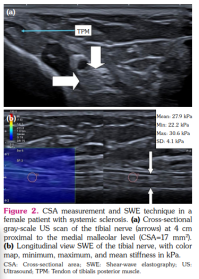

Tibial nerve was examined in the transverse and longitudinal planes at a distance of 4 cm proximal to the tip of the medial malleolus. The correct imaging plane was confirmed by tendinous landmarks, such as the flexor digitorum longus and flexor hallucis longus tendons, and the posterior tibial vessels.[16] CSA was measured by the use of a continuous boundary trace of the nerve directly over the epineurium on transverse images (Figures 1, 2).

Shear-wave elastography was performed by careful handling of the transducer during transport and mounting to avoid compression force. The skin surface was coated with ample coupling gel before placing the transducer, which was used with light force and kept stable during image acquisition. TN was first identified transversely, and then the transducer was rotated 90° to acquire a longitudinal image of the nerve in the parallel direction to the fiber orientation.[16]